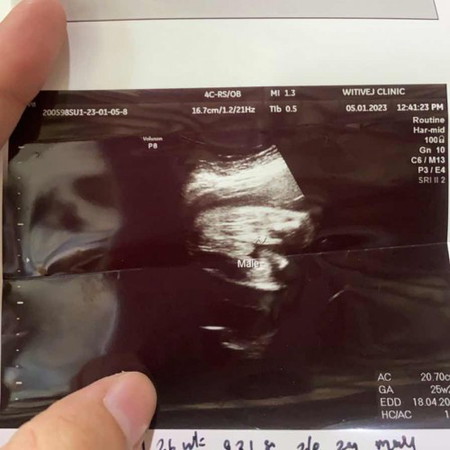

ไปอัลตร้าซาวน์มา แม่ๆช่วยดูหน่อยค่ะ ว่าเพศไหน หมอบอก ผช คนแถวบ้านชอบมาพูดว่าเห็นเป็นชายรอดูตอนคลอดออกมาเชื่อสิเป็น ผญ แล้วเราอยากได้ลูกชายพอดีค่ะ ไม่ชอบเลย

น่าจะ ผช หรือป่าวคะไม่แน่ใจ